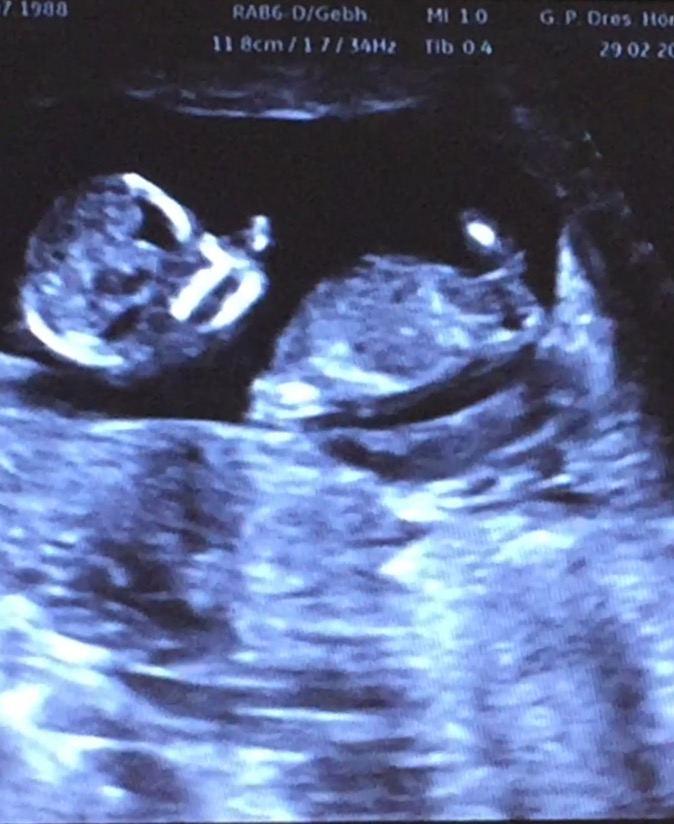

my doctor is leaning Boy because of something sticking out looking at the potty Shot, but said it was early... He did not know the Nub Theory, so I'm asking you Girls, is this a reliable picture? I have a video and am trying to cut some good Positions, but Baby is turning round all the Time...

Attachment 30177